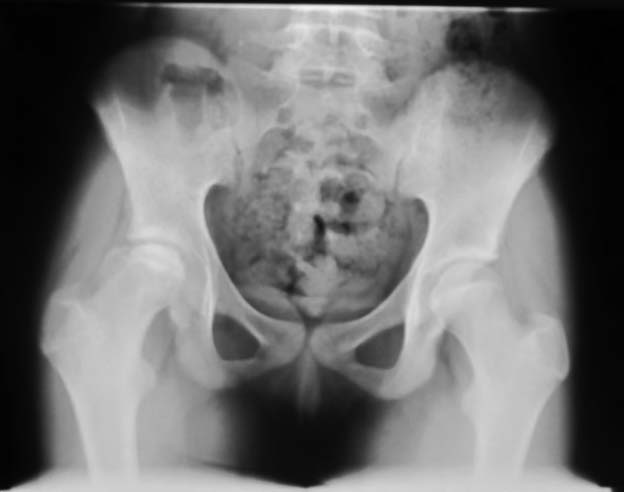

Обратилась пациентка 12 лет, 7 месецев назад стали замечать хромоту.

Лечилась консервативно. Снимки в приложении. Выражена хромота, резко ограничены отведение и ротационные движения бедра. Чем можно помочь сейчас или "поезд ушел"? Прогноз? Буду блогодарен любым соображениям.

Аршак! Сделай КТ, лучше трехмерку. Дальше будем решать. Процесс по восстановлению эпифиза завершился, но с явной деформацией. АИФ

У меня более взрослые больные с последствиями и поэтому вопрос к педиатрам-специалистам по заболеванию Пертес. Не вызывает ли сомнения диагноз? Меня смущает небольшой срок истории и возраст пациентки. Болезнь может встречаться до 12 летнего возраста, но к этому времени у многих заканчиваются все стадии развития заболевания, включая вовлечение в процесс ацетабулума. Обычно процесс течение заболевания немного дольше, чем "7 месецев назад стали замечать хромоту".

Встречается ли заболевание без характерного склероза с молниеносным течением в 12 летнем возрасте? По-моему, изчезновение головки в короткий срок характерно для септических состояний, и поэтому на первое место в дифференциальной диагностике я бы поставил на септический артрит? Заново собрать анамнез на восспалительный процесс, анализы, пункция?

In this age prognosis is bad , but I think that she will improve after Vagus osteotomy -the goal is to remove necrotic part of the head from the weight bearing edge of the acetabulum